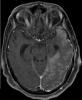

• Angel Cano Abascal | 22-Apr-2020

Lactante mujer con antecedentes de hemorragia intraventricular perinatal grado IV e hidrocefalia secundaria siendo portadora de una derivación ventriculoperitoneal.

A los 7 meses de edad comenzó con espasmos y un trazado hipsarrítmico en el V-EEG. Se inició...

Neurología: EpilepsiaEtiología: Metabólico | Tóxica-yatrogeniaDiagnóstico final: Anomalías cerebrales en relación con VigabatrinaNivel de certeza: